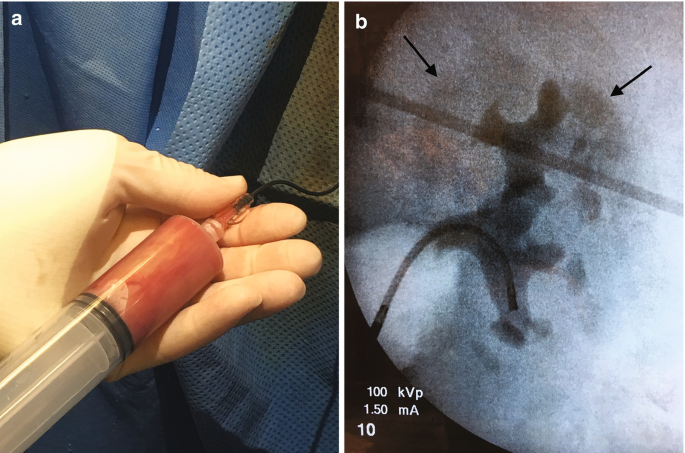

有感染和梗阻体征的患者必须怀疑肾盂积脓 (a),如这种化脓性肾盂抽吸物所示。在这种情况下,高压冲洗可以通过肾盂静脉回流将微生物从尿液置换到血流中,产生尿脓毒症。由于输尿管镜检查期间高压造影剂冲洗(b),可以看到具有造影剂的肾实质轮廓(箭头)。